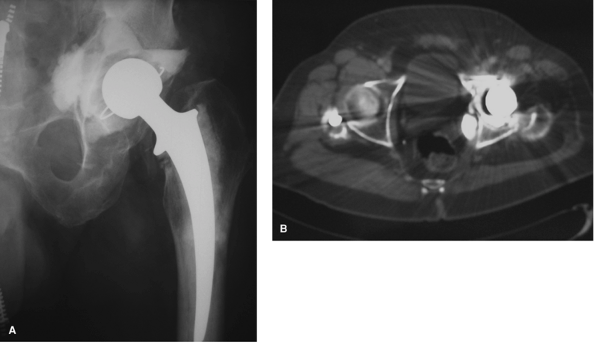

Figure 2-18 Preoperative radiograph of a 68-year-old man with an infected left total hip arthroplasty (A) with retained intrapelvic cement confirmed on CT scan (B) that required removal during surgery.

failed acetabular component, CT scans can aid in determining the

vasculature (Fig. 2-18A, B). A CT scan may also be useful for assessing component position in the clinical setting of recurrent prosthetic instability.

The evaluation of acetabular or femoral component ante- version in

relationship to fixed bony landmarks may provide useful information